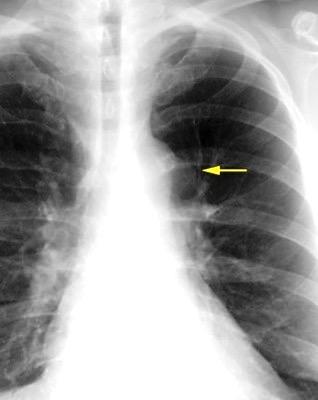

30 años

Borramiento de la banda PARA-aórtica por AdenoCa. de LII, no visible en 2005

Colapso de LII. TC: secreciones bronquiales.

Endoscopia tapón mucopurulento extraído

Borramiento parcial por Ca. epidermoide.